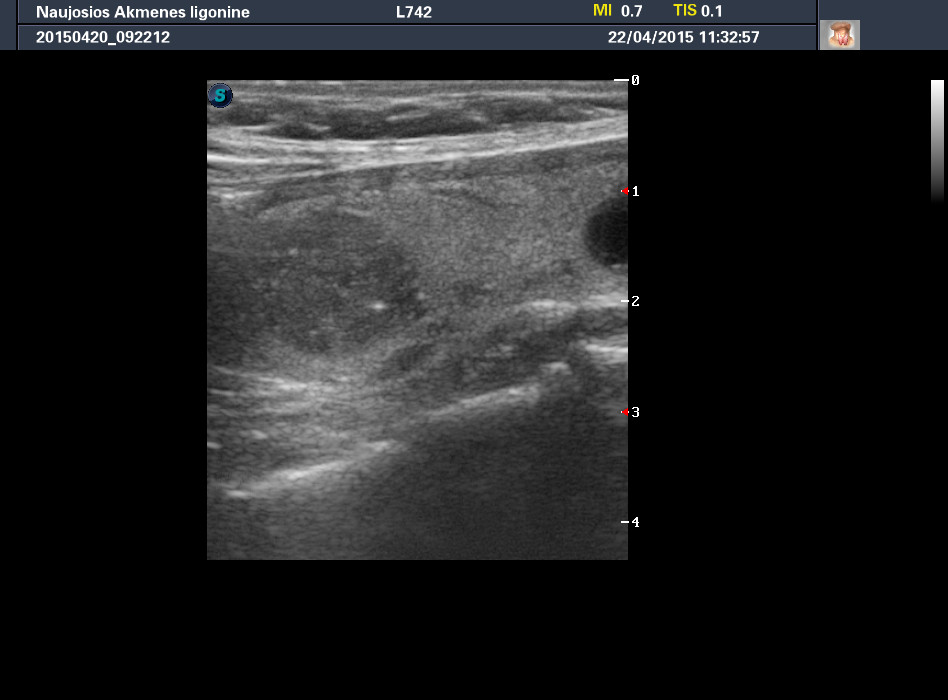

Случай 2

Женщина 61 год, жалоб нет. Рост узла за год +1 мм. Регионарные ЛУ не увеличены.

apr222015113257_27.jpg

phpBB [video]

1-й узел злокачественный, а 2-й ,скорее всего, доброкачественный. Но,понятное дело, нужна пункция и было бы здорово узнать результат.

Mattiola писал(а): И,простите, что за исследование на сканах, не на видео? Я такого не делаю и,к сожалению, не знаю,как интерпретировать его(

Эластография. http://www.medison.ru/si/art380.htm